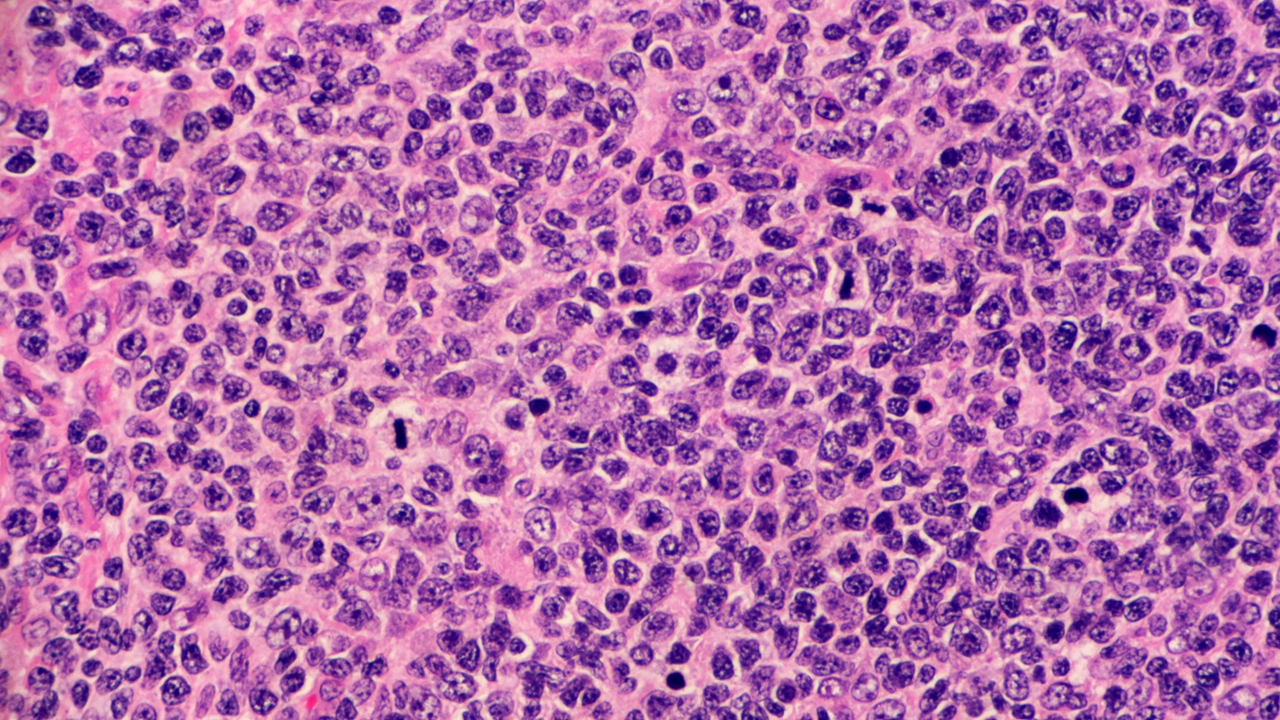

En el estudio fase II, TRASCEND-FL, lisocabtagene maraleucel (liso-cel) mostró un alto porcentaje de respuestas globales y duraderas en pacientes con linfoma folicular en recaída o refractario (R/R)

La FDA, basado en los resultados positivos del estudio TRANSCEND-FL, aprobó de forma acelerada la terapia liso-cel para adultos con linfoma folicular R/R, quienes han sido tratados previamente con dos o más líneas de terapia sistémica (que incluya un anticuerpo anti-CD20 y un agente alquilante), y que cuentan con una función ósea adecuada para recibir quimioterapia linfo-depletiva, además de tener un estado de desempeño ECOG de 1 o menos.